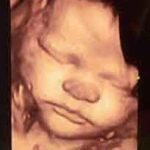

Yukarıdaki görselde, 36 haftalık gebeliğe ait tombul yanaklı bir erkek bebeğin 36 haftalık 3 boyutlu resmini görmektesiniz 🙂

Gebeliğin 36. haftasında bebeğin yanakları, kolları ve bacakları tombullaşmaya (tombul insan yavrusu olma yolunda ilerliyor 🙂 36. haftalık hamilelikte anne karnındaki bebeğiniz eski sıska görünümünden yavaş yavaş kurtuluyor. Hızla doğum kilosuna yaklaşıyor. Ultrasonda bebeğinizi kordona dolanmış bir halde görebilirsiniz. Endişeye gerek yok, bu bütün bebeklerin başına gelen bir durum ve bebeğe herhangi bir zararı yok. İçinizi rahatlatmak için mutlaka doktorunuza sorun elbette.